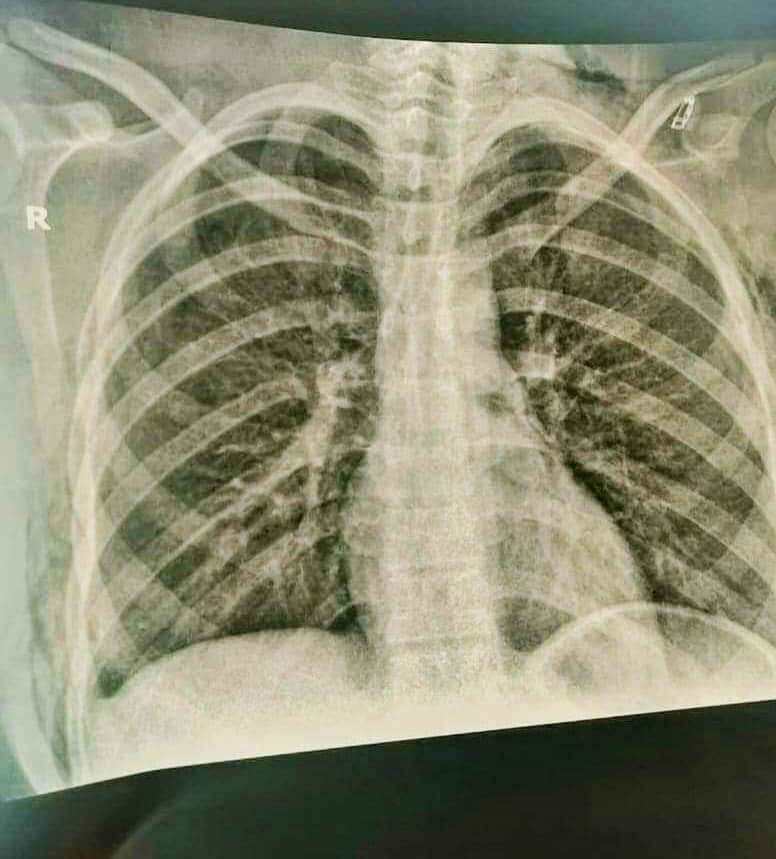

نجح فريق جراحة الأطفال بمستشفى الأطفال التخصصي بدمسنا بمحافظة البحيرة، بقيادة الدكتور محمود عبد الهادي، أستاذ جراحة الأطفال بجامعة الأزهر، والفريق المعاون من استئصال العصب السمبثاوي الصدري عن طريق منظار الصدر الدقيق جدا بفتحة لا تتعدى مليمترات في أقل من نصف ساعة.

وخرجت المريضة بحالة مستقرة لتمارس الحياة اليومية بشكل طبيعي، وتقدم الدكتور محمود طلحة، وكيل وزارة الصحة بالبحيرة، بالشكر لفريق جراحة الأطفال بالمستشفى ولإدارة المستشفى وتمنى لهم المزيد من التقدم والازدهار والنجاح، وتقديم كل وسائل المساعدة للرقي والتطور لمستشفى الأطفال التخصصي بإشراف الدكتور إيهاب بركات، مدير مستشفى الأطفال التخصصي.